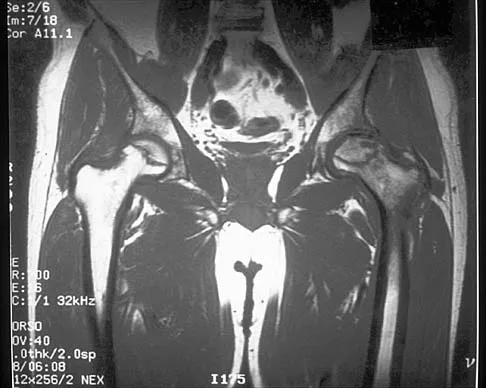

An axial T1-weighted MRI scan of the pelvis is shown in Figure 35. Which of the following structures is enclosed by the circle?

Explanation